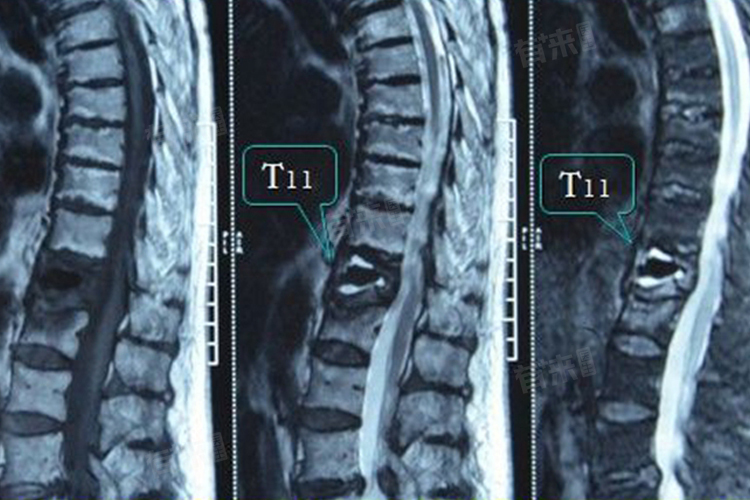

T11椎体即第十一胸椎,是人体脊柱中的一个重要组成部分。在解剖学中脊柱被分为颈椎、胸椎、腰椎、骶椎和尾椎五个部分,其中胸椎共有12节,编号从T1至T12,T11椎体就位于这12节胸椎中的第11节。

- T11椎体位于胸椎和腰椎的结合部,上方紧邻第十胸椎,下方连接第十二胸椎并靠近腰椎,使得T11椎体在脊柱的转折区域,承受着较大的力学压力。

由于T11椎体位于脊柱的胸腰结合部,这一位置使得它容易受到外伤或劳损的影响。因此在临床上T11椎体的损伤或病变并不罕见,常见的疾病包括T11椎体骨折、胸椎间盘突出症等。这些疾病可导致疼痛、活动受限等症状,严重时甚至可能影响呼吸功能。